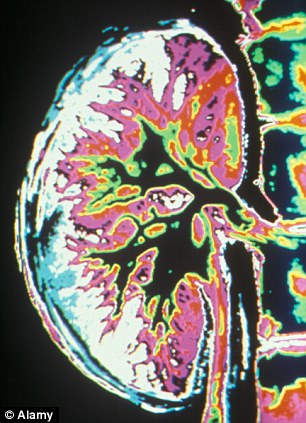

الكلى الميتة تعود إلى الحياة

يتم إعادة الكلى الميتة الى الحياة في المختبر كما إتخذ العلماء الخطوة الأولى لإنشاء أعضاء جديدة للبشر

تمكن العلماء من تحقيق إعادة الكلى الميتة الى الحياة.

ذلك السبق التقنى يمكن أن يؤدي إلى أن المرضى سيقومون بتنمية الكلى الخاصة بهم , بدلا من الاعتماد على المانحين.